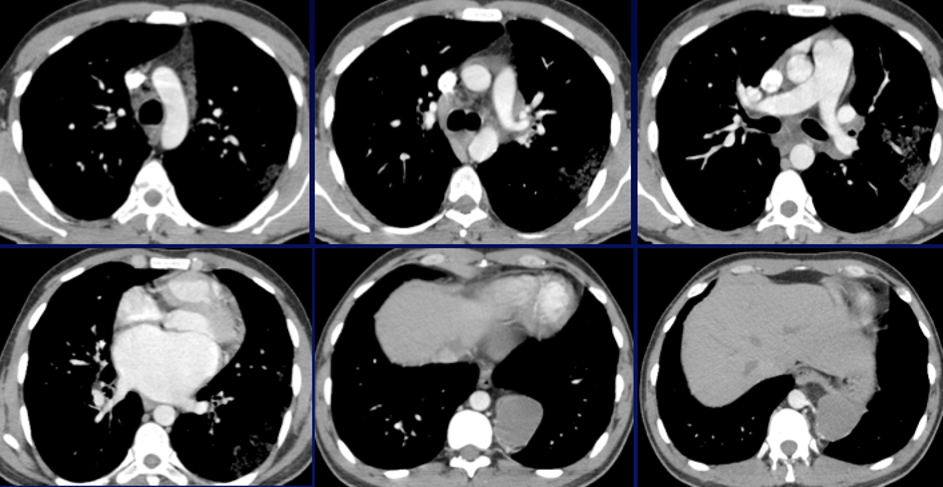

Jeune homme de 27 ans

Hémoptysies de faible abondance

Récidivantes depuis 3 mois avec dyspnée d’effort

Anémie hypochrome microcytaire à 6g/dl